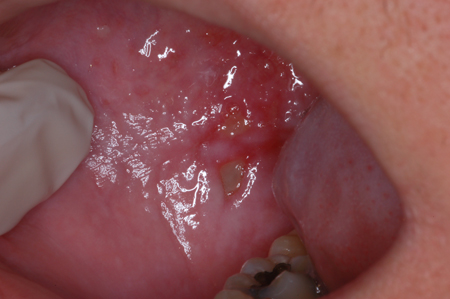

Мукозит: дорсолатеральный язык

Из преподавательской коллекции Раджеша В. Лалла, DDS, PhD, CCRP, DABOM; используется с разрешения